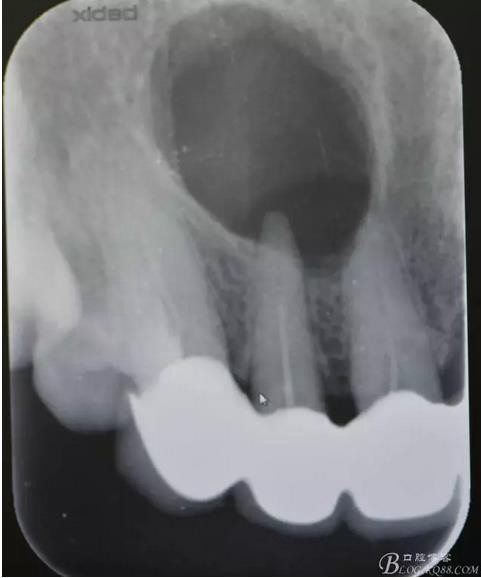

圖1.術(shù)前的根尖片影像檢查:11、12根管治療不完善